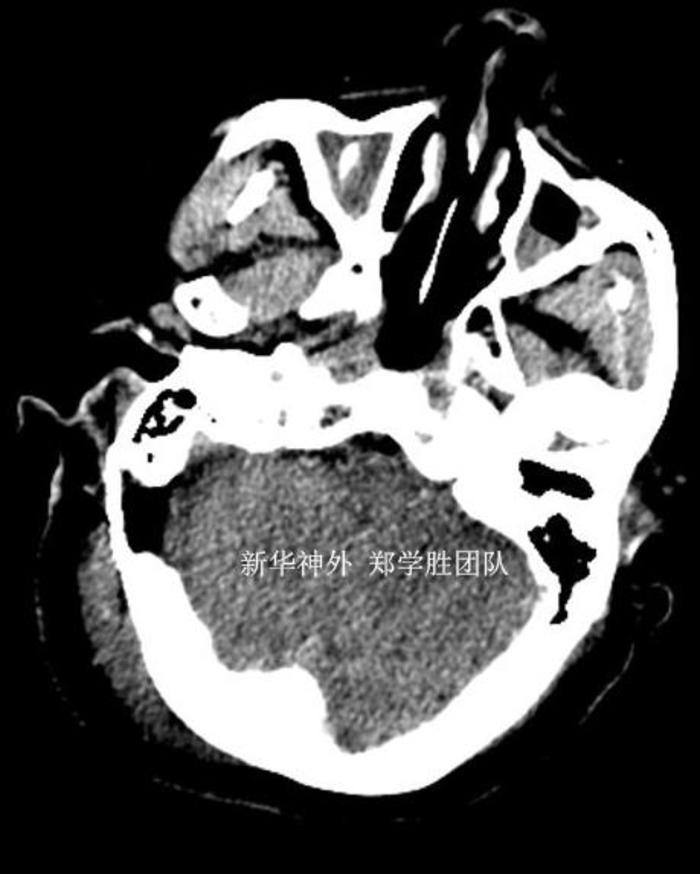

另外,由于心脏支架,不能做磁共振,术前只能做CT检查,CT不能看到三叉神经血管压迫的情况,只能排除有没有脑肿瘤。箭头所指的是三叉神经位置。

手术顺利,术中发现是小脑上动脉呈袢状严重压迫三叉神经,予以完全减压。术后复查CT,手术部位没有任何出血,予以中性治疗。